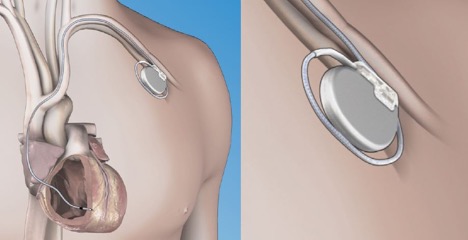

Kako se ugrađuje pejsmejker

Operacija se standardno izvodi u lokalnoj anesteziji. Sam pejsmejker je generator koji proizvodi struju i ugrađuje se ispod kože. Najčešće sa leve strane, ispod leve ključne kosti, pejsmejker se stavlja u prethodno pripremljen „džep“ pod kožom. Elektrode se plasiraju kroz odgovarajuće vene, pod kontrolom rendgena, do srca, tačnije do desne komore i pretkomore, a u slučaju resinhronizacionog pejsmejkera, elektroda za stimulaciju leve komore se plasira kroz površne vene na srcu (coronarni sinus). Kada se konstatuju zadovoljavajući električni parametri, elektrode se „ušrafljuju“ u srčani mišić.